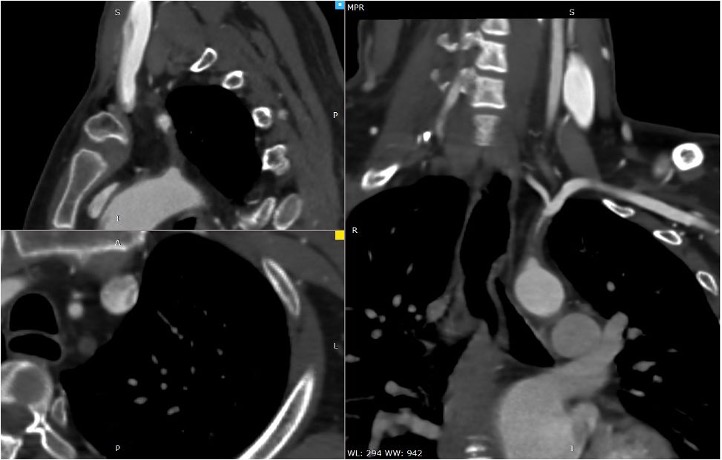

Relevant Test Results Prior to Catheterization

Duplex ultrasonography showed monophasic waveform in the left axillary, brachial, radial, and ulnar arteries. Retrograde flow was observed at the left vertebral artery, findings consistent with left subclavian steal syndrome. Computed Tomography Angiography (CTA) showed non calcified plaque with total occlusion from ostial left subclavian artery up to just before the origin of vertebral artery, with a tapered distal segment, and approximately 25–26 mm in length.